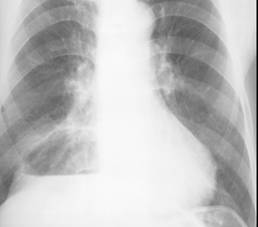

Fig. 15 – Abces pulmonar stang (imagine hidroaerica parahilar stanga cu nivel mare de lichid si pereti grosi imprecis delimitati)